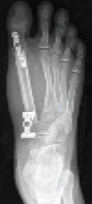

手术当天,麻醉手术部阳婷婷医生凭借丰富临床经验,顺利完成椎管内麻醉。在韩学哲与边卫国教授的指导下,杨卫周与刘俭涛医生精准切除受累的第一跖骨与内侧楔骨,并与整形外科何林医生顺利切取长约11厘米的小腿处带血管蒂腓骨,再通过“移花接木”式技术,将其移植至脚趾缺损部位。通过精细的显微外科技术,团队成功吻合足背血管,恢复移植骨块血运。在多科室通力协作下,手术圆满完成。

术后,在骨科护理团队的精心照护下,Adnan恢复良好,已于近日康复出院并顺利返回孟加拉国。